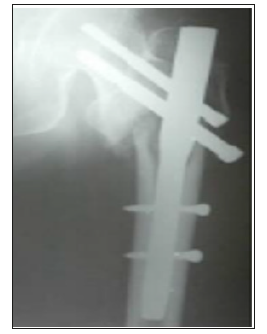

Follow up: Tablet Risedronate 35mg once weekly for 12weeks were given to improve the bone mineral density in patients with severe degree osteoporosis. All the patients were advised to completely weight bearing after 10-12 weeks of post-operative period. All patients were followed up at the end of 1,2,6,12 and 18 months. At each follow up, the radiographs of upper femur and hip were taken to assess the fracture union and the complications. The functional results were calculated according to Harris hip score. All patients enrolled in the study were offered with surgical implant removal at an average of 18months post-surgical procedure who showed the clinical and the radiological union of fractures and improved functional quality of life (Figures 5 & 6).

Figure 5:Trochanteric fracture fixed with proximal femoral nail.

Figure 6:Subtrochanteric fracture fixed with proximal femoral nail.